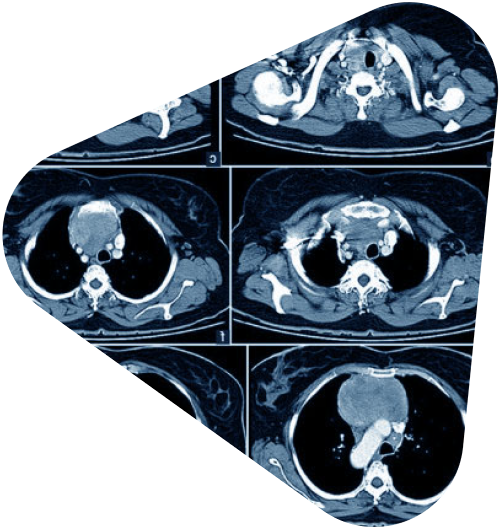

Мы живем в эпоху стремительных технологических изменений, и медицина не является исключением․ В последние годы искусственный интеллект (ИИ) все активнее проникает в различные области здравоохранения, предлагая новые возможности для диагностики, лечения и профилактики заболеваний․ Одной из наиболее перспективных областей применения ИИ является пульмонология, где он может значительно улучшить интерпретацию компьютерной томографии (КТ) легких․

КТ легких – это мощный инструмент, позволяющий визуализировать структуру легких и выявлять различные патологии․ Однако интерпретация КТ изображений требует высокой квалификации и опыта от врача-рентгенолога․ И даже самые опытные специалисты могут допускать ошибки, особенно при анализе больших объемов данных․ Именно здесь на помощь приходит ИИ․

Когда мы говорим об ИИ в пульмонологии, чаще всего подразумеваем алгоритмы машинного обучения, которые обучены на огромных массивах КТ изображений легких․ Эти алгоритмы способны распознавать различные паттерны и признаки заболеваний, такие как узелки, затемнения, эмфизема и другие․ И что самое важное, они могут делать это с высокой точностью и скоростью․